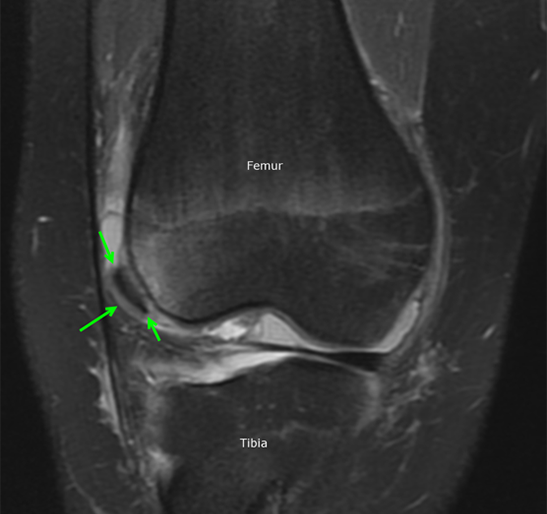

The diagnosis is typically made by history and physical examination. Knee x-rays are obtained initially to look for bone injuries, but cannot fully show the extent of soft tissue damage. For this reason, an MRI is performed soon after to assess the ligaments and cartilage and help determine whether surgery will be necessary. The MRI will also show underlying anatomical features that may predispose to the instability of the patella. If there is a significant injury to the cartilage covering the bone, a loose fragment in the joint, or tearing of the main ligament that stabilizes the patella, surgical treatment is recommended.

Luckily for Patrick Mahomes, the MRI did not show damage to the cartilage or ligaments. He was treated medically with physical therapy and able to return to play in a couple of weeks. The child with the MRI below was not as fortunate and required surgery to repair the patella. After a patellar dislocation, there is an increased risk of a recurrent dislocation, so continued follow-up and therapy are necessary.